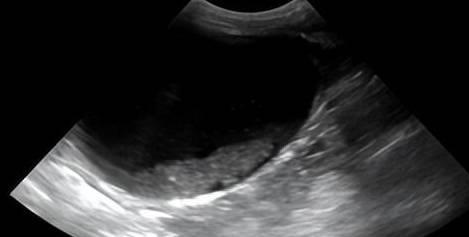

B超泌尿系统检查是利用超声波在人体内部传播时产生的回声来观察器官形态、大小、位置等的一种无创检查方法。通过B超检查,医生可以直观地了解泌尿系统的健康状况,及时发现并诊断疾病。

检查过程:医生将B超探头放置于患者下腹部,通过探头发射超声波,观察泌尿系统器官的形态、大小、位置等。

检查结果分析:医生根据B超图像,对泌尿系统器官进行评估,判断是否存在异常。